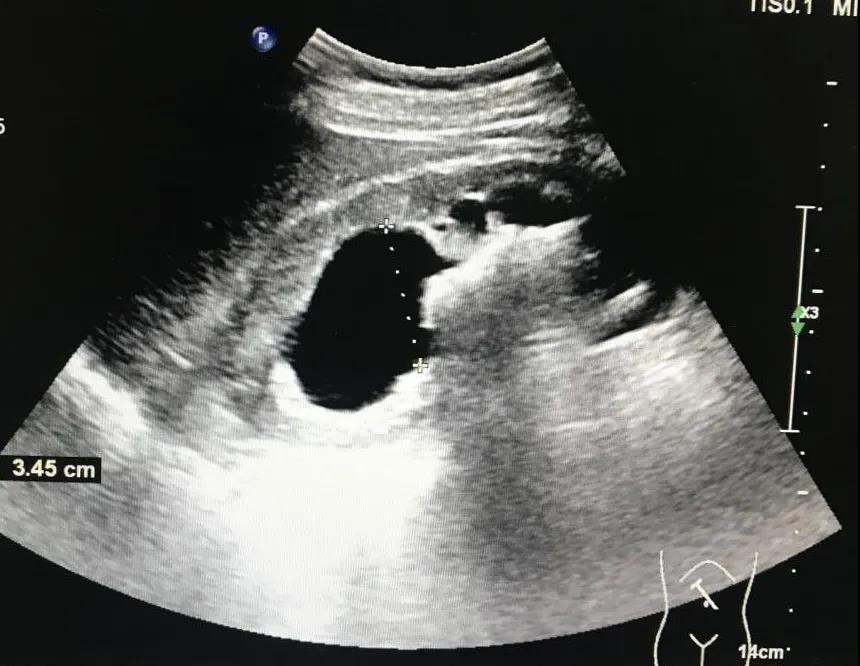

腎竇內(nèi)探及大小不等的強(qiáng)回聲光團(tuán),后方伴有聲影,體積較小的結(jié)石及一些質(zhì)地比較疏松的結(jié)石后方可不出現(xiàn)聲影或聲影比較淺。如果結(jié)石比較大引起梗阻會(huì)出現(xiàn)腎盞或腎盂積水的聲像圖改變(見(jiàn)圖1)。由于結(jié)石的大小、成分及形態(tài)各不相同,其圖像表現(xiàn)也有不同:

圖1:結(jié)石后方伴聲影,梗阻引起腎盂積水